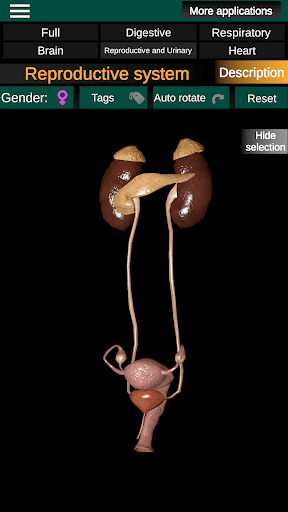

* Reproductive system, which includes the male and female reproductive organs.

* Compare male and female organs.

* Descriptions of each organ.